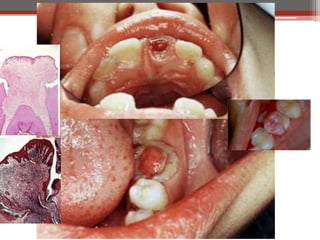

Chronic Hyperplastic Pulpitis

Clinical Features:

• Opened cavity.

• Red pinkish soft nodule protruding

• Starts as chronic or

into the cavity.

acute.

• Almost in children and young adults.

• Wide apical foramen

• Relatively insensitive to manipulation.

[Children].

• Most common in deciduous molars.

• Must be differentiate from gingival

polyp.

Histopathological Features:

• The polyp consists of granulation tissue.

• It contains delicate connective tissue, fibers and blood vessels.

• Mononuclear inflammatory cell infiltration.

• The polyp is covered with SS epithelium.

• Treatment: RCT or extraction of the tooth.

Chronic Hyperplastic Pulpitis Etiology: ClinicalFeatures: • Opened cavity. • Red pinkish soft nodule protruding • Starts as chronic or into the cavity. acute. • Almost in children and young adults. • Wide apical foramen • Relatively insensitive to manipulation. [Children]. • Most common in deciduous molars. • Must be differentiate from gingival polyp. Histopathological Features: • The polyp consists of granulation tissue. • It contains delicate connective tissue, fibers and blood vessels. • Mononuclear inflammatory cell infiltration. • The polyp is covered with SS epithelium. • Treatment: RCT or extraction of the tooth.